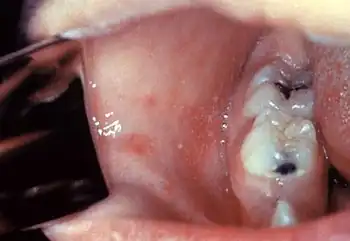

Symptoms typically begin 7–14 days (typically 11-12 days) after exposure with a prodrome of fever, malaise, and cough.[5][3][6] The fever with measles increases in a stepwise fashion and peaks at 103 °F (39 °C) - 105 °F (41 °C).[5] After one to two days of prodromal illness, Koplik spots appear inside the cheeks opposite the molars as clusters of white lesions ("grains of salt") on reddened areas. They are pathognomonic for measles, but are present for only a short time and therefore are not always seen.[3] The classic symptoms include a fever, cough, coryza (head cold, fever, sneezing), and conjunctivitis, referred to as "the three C's", and a maculopapular rash.[26]

Koplik's spots on the third pre-eruptive day -